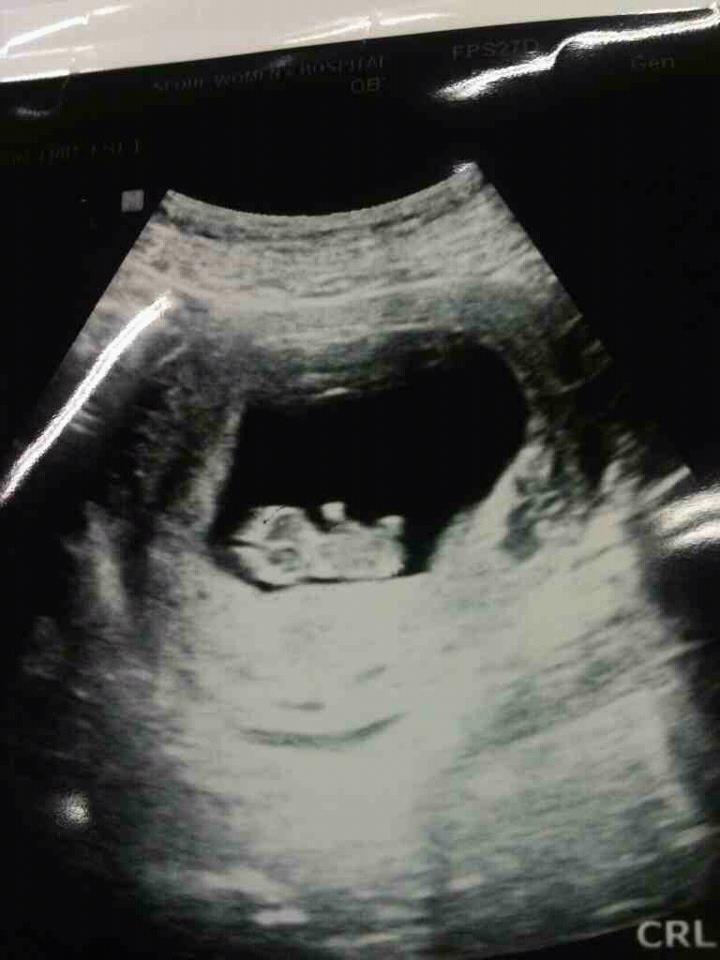

¿ÜÇҾƹöÁö ¶«¿¡ ¼Ó»óÇØ ÇÏ´Â ³»°Ô ¿ô¾îº¸¶ó°í Å«¾ÆµéÀÌ 9ÁÖµÈ ¼ÕÀÚ ¼ø¹é»çÁøÀ» º¸³Â´Ù.

µ¿¿µ»óÀ¸·Î ¾ÆÀ̰¡ ¿òÁ÷ÀÌ´Â °É ºÃ½À´Ï´Ù.

¼Õ¹ßÀ» ¿òÁ÷À̰í ÀÖ´õ±º¿ä.

Á¶±ÝÀÖÀ¸¸é ¼ºº°µµ ¾Ë°ÚÁö¿ä?

Áö±Ý ÀÌ·¸°Ô ¹î¼ÓÀÇ ¾Æ°¡ ¿òÁ÷ÀÓ±îÁö ´Ù º¸´Â ¼¼»ó¿¡